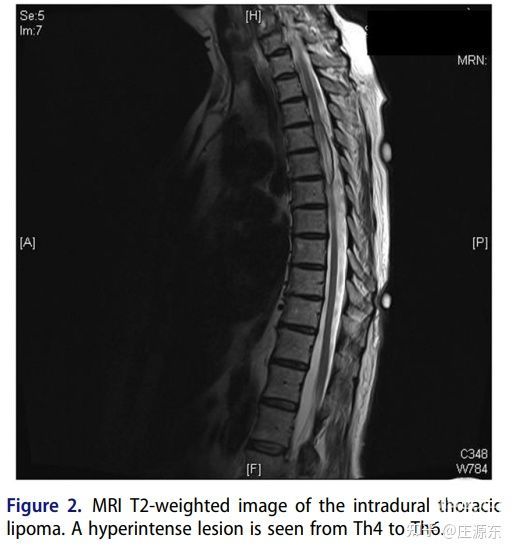

MRI T2像可见硬膜内脂肪瘤。T4-6高信号影。